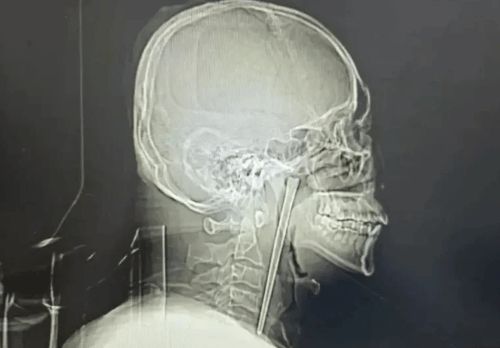

Yemək çubuğunu udan kişi 8 il həkimə getməyib

Çubuq udduqdan sonra kişi cərrahiyyə əməliyyatından qorxduğu üçün həkimə müraciət etməkdən 8 il yayınmağı bacarıb.

Medicina.az xəbər verir ki, Çindən olan cənab Vanq 8 il əvvəl təsadüfən paslanmayan poladdan hazırlanmış çubuq udub. Boğazına ilişib qalan yad cismin çıxarılması üçün cərrahiyyə əməliyyatının lazım olacağından panikaya düşən Vanq xəstəxanaya getməyib.

Beləliklə, kişi bütün bu illər ərzində dözməli olub və çubuğu qida borusunda gəzdirib.

Vanq şanslı idi, çünki çubuq boğazına ciddi zərər vermədi. Müalicəyə gəldikdə isə, həkim xəstənin fobiyasını nəzərə aldı və minimal invaziv cərrahiyyə əməliyyatı ilə çubuğu çıxardı.